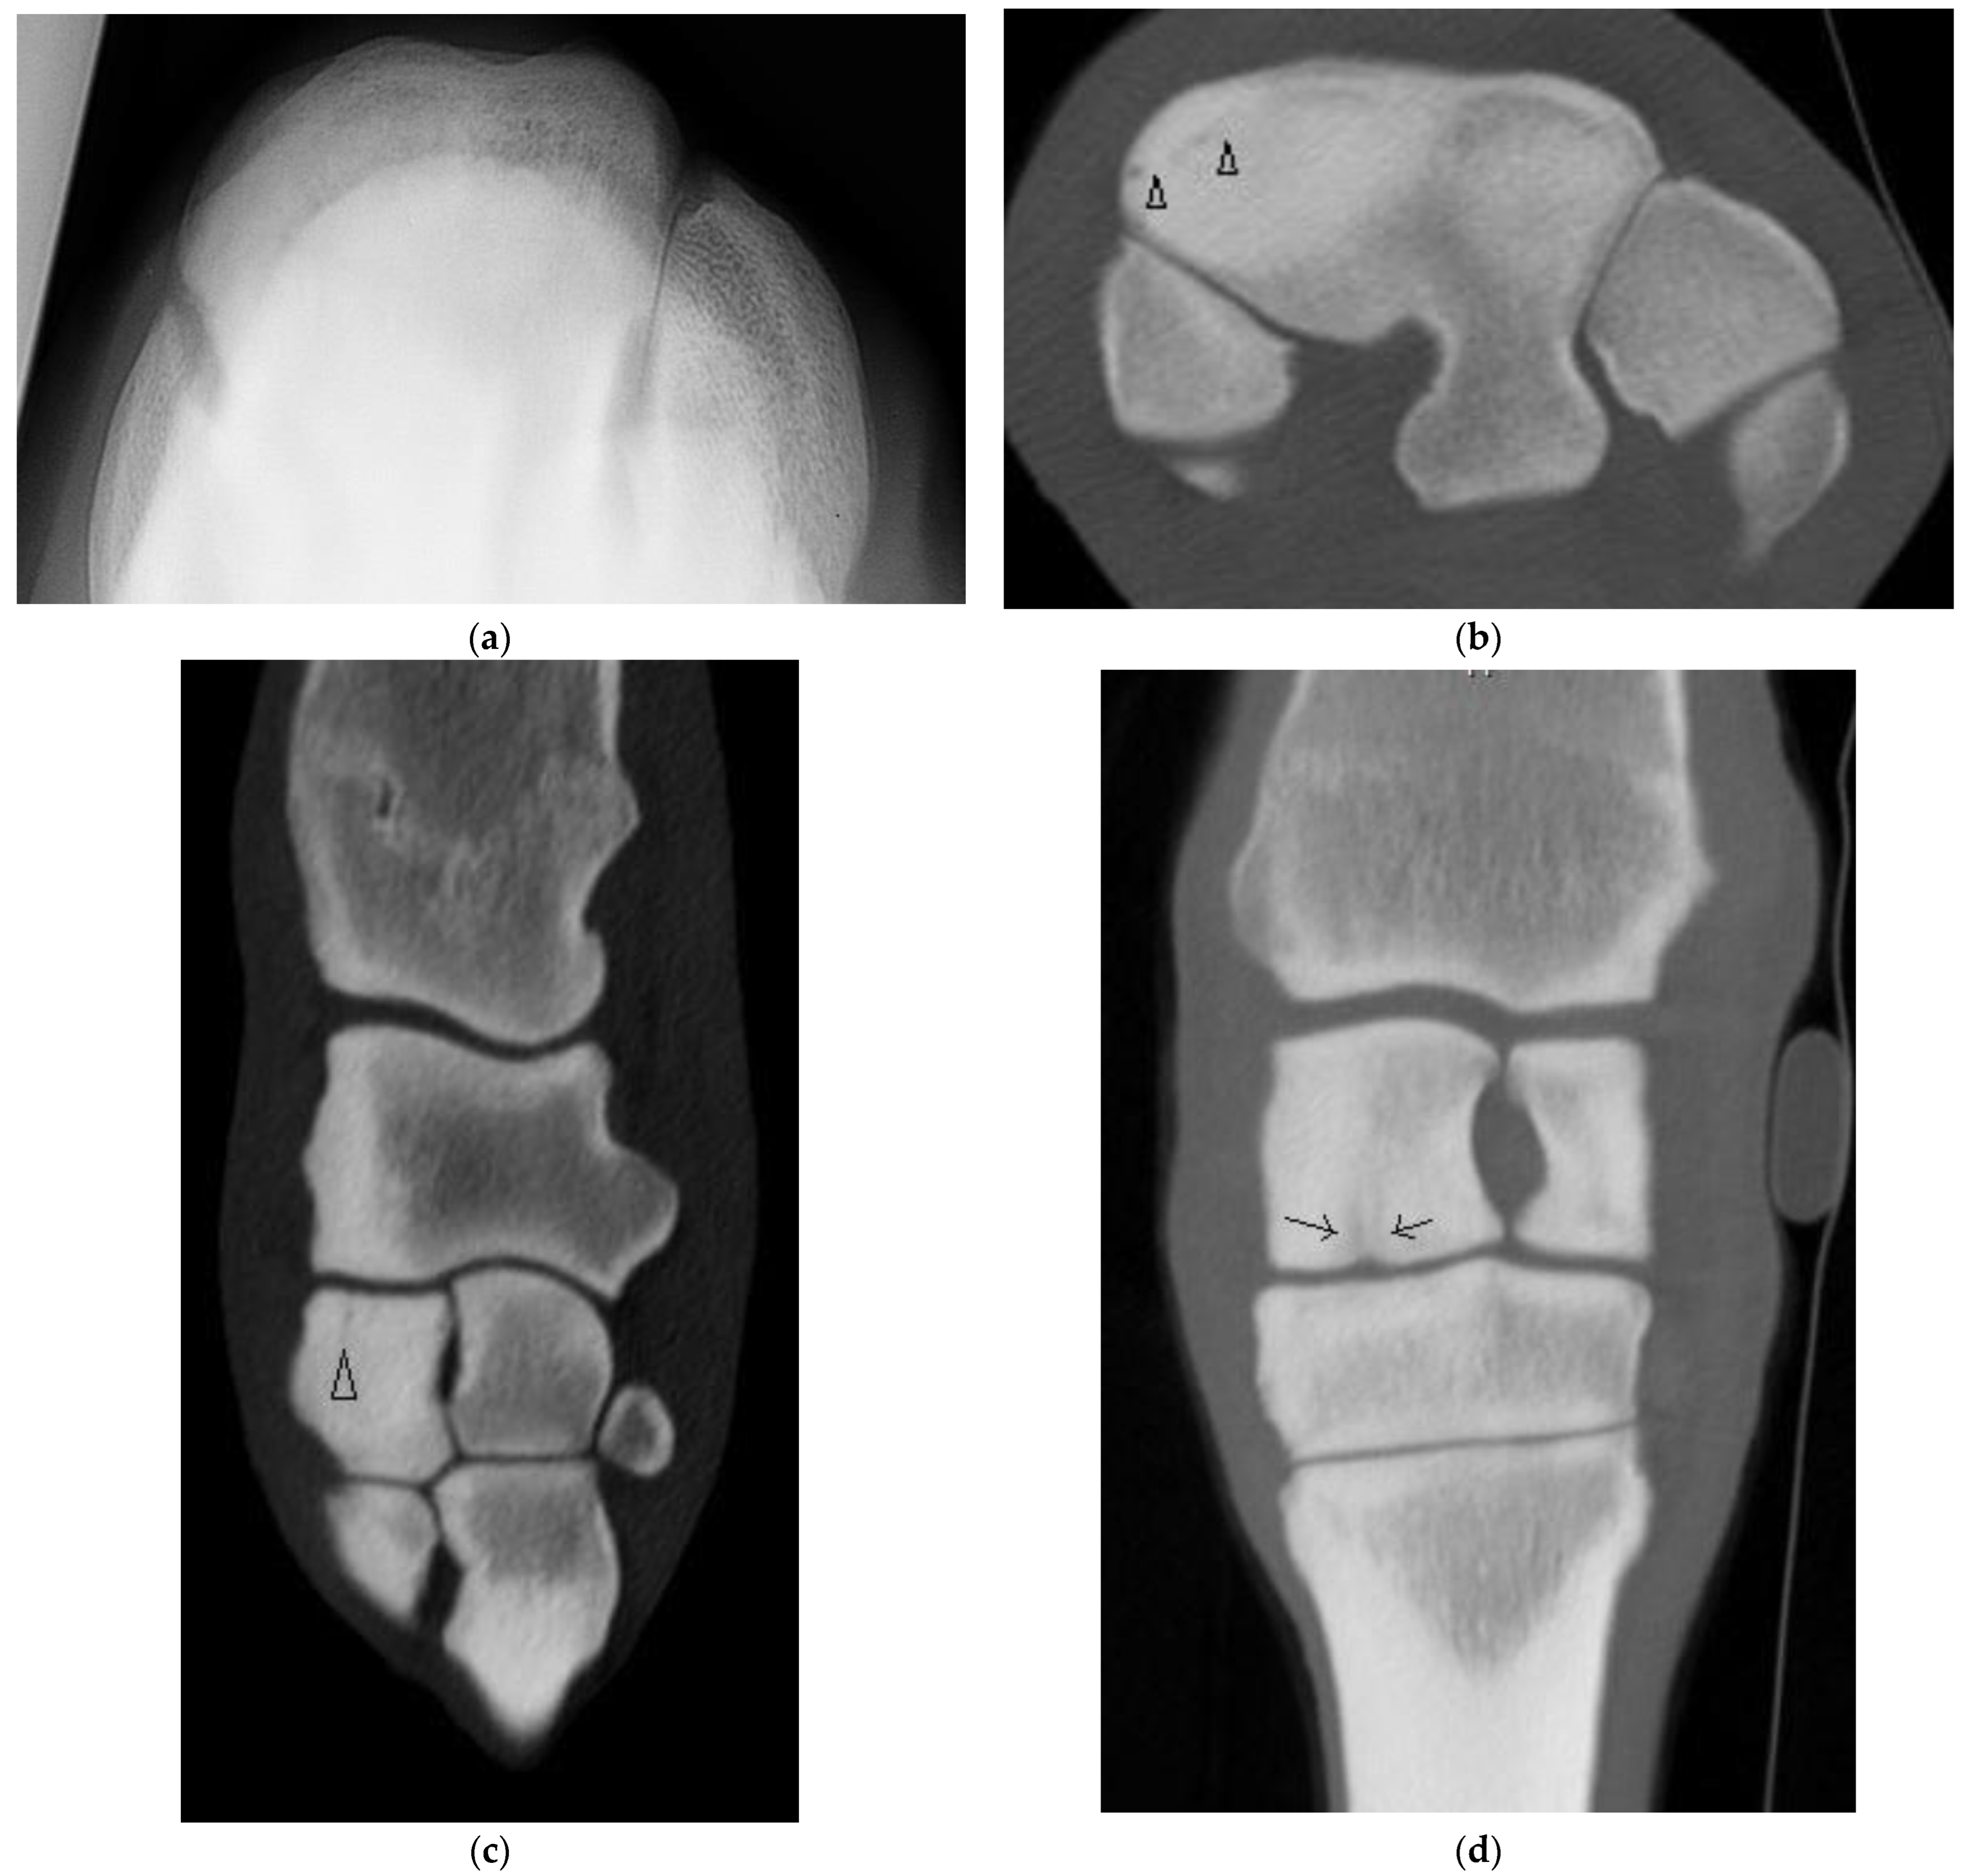

Five horses had a sagittal fracture of the RaF (one incomplete, three complete, and one unsure on DR and CT but determined most likely incomplete); all lacked comminution. In one horse, both observers were unsure whether the incomplete RaF Fx was sagittal or corner on DR; CT confirmed a sagittal Fx. In another horse, both observers were unsure whether the Fx was sagittal or corner and whether the Fx was complete. In both cases, CT confirmed fracture configuration as sagittal and identified additional lesions not identified on radiographs (Supplementary Table S3). Of the three horses with complete sagittal fracture, all had some lysis of the proximal SCB at the fracture margin within the mid RaF (Figure 3) and 2 had additional lesions including DCL and OF not evident radiographically.

Four horses had complete fractures of variable configuration with both sagittal and frontal components. Three were corner Fx of the RaF and two of these had substantial additional fissures or fractures detected only on CT (Figure 4). The other horse had a complete Fx of both facets, with orientation that was sagittal in the RaF and frontal palmar to the InF (Figure 5); a configuration not recognized on DR.

Figure 3. Images of the right carpus of a 3-year-old thoroughbred filly. (a) Transverse CT image of the distal row of carpal bones reveal a sagittal slab fracture of the radial facet of the third carpal bone (C3). This slice through proximal C3 reveals a large subchondral lucency within the radial facet that was not evident radiographically. (b) A transverse CT image through mid C3 reveals a partial thickness subchondral lucency at the articulation with the second carpal bone (C2) (arrow) and a small dorsal cortical lucency (white arrow). (c) Flexed dorsoproximal-dorsodistal oblique radiographic view of the distal row of carpal bones. The sagittal fracture and subchondral lucency at the articulation with C2 is evident but the subchondral lucency mid radial facet is not.

Figure 4. Images of the left carpus of a 6-year-old thoroughbred gelding. (a) Transverse CT image through the proximal portion of the distal row of carpal bones. A comminuted corner fracture of the radial facet of the third carpal bone (C3) is evident. (b) A transverse CT image further distad reveals a large frontal fissure (arrow head). (c) Flexed dorsoproximal-dorsodistal oblique radiographic view of the distal row of carpal bones. The comminuted corner fracture was evident radiographically but the frontal fissure was not.